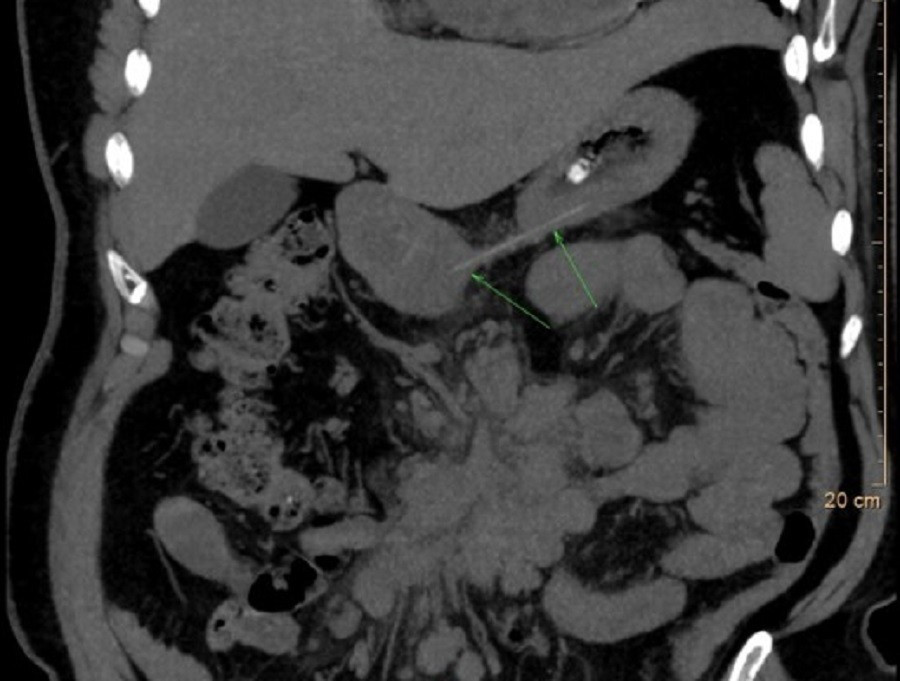

Chiếc xương cá (vị trí mũi tên) là thủ phạm khiến người bệnh phải nhập viện

Kết quả nội soi Tai Mũi Họng ghi nhận tình trạng phù nề nhiều ở vùng sụn phễu trái. Nội soi dạ dày – thực quản không phát hiện dị vật trong lòng ống tiêu hóa. Tuy nhiên, phim X-quang cổ nghiêng cho thấy hình ảnh nghi ngờ có dị vật. Để đánh giá chính xác, các bác sĩ chỉ định chụp CT và phát hiện một mảnh xương cá kích thước khoảng 1 x 22 mm đã xuyên ra khỏi đường tiêu hóa và cắm sâu vào thùy trái tuyến giáp.